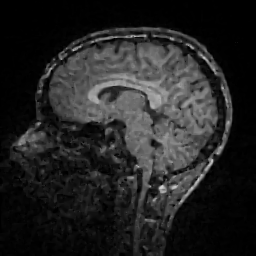

Improving image reconstruction from a sparse set of known pixels was the main motivation behind our work. Therefore, we applied it to two well-known natural images, lena and peppers, as well as to a medical image, a slice of a weighted brain MR scan (t1slice). For lena, we kept a random subset of only of the pixels. Due to the lower resolution of the peppers and t1slice images, we kept and , respectively.

Results for lena are shown in Figure 2, for peppers in Figure 3, and for t1slice in Figure 4. A quantitative evaluation in terms of MSE and AAE is presented in Table 4.1. In terms of the numerical results, our proposed method produced a more accurate reconstruction than any of the competing approaches. Visually, there is a clear difference between second-order (EED) and fourth-order approaches (Li1, Li2, FOEED). Especially, we found that the shapes of edges were reconstructed more accurately. For example, we noticed this around the shoulder and hat in the lena image (Figure 2). Similarly, the white and grey matter boundaries were better separated in the t1slice (Figure 4).